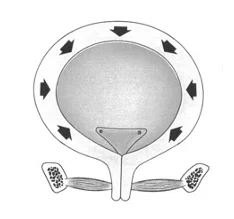

Stresová inkontinencia moču

Hyperaktívny mechúr